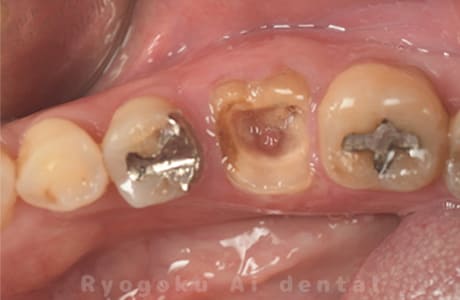

Case10

-

- 原因

- 右上6番パーフォレーション

- 治療内容

- マイクロエンド治療(パーフォレーションリペア)、ゴールドクラウン修復

- 治療費用

- 297,000円

右上奥歯を他院で抜歯と言われ、残して欲しいとのことでご来院された患者様です。穴が空いている部分をMTAでリペアを行い、再度マイクロスコープ下で根管治療を行い、ゴールドクラウンで修復しました。経過も良好で、大変満足して頂けました。

<リスク・副作用>

術後は痛み、腫れ、痺れなどの副作用が生じる場合があります。症状が再発する可能性があります。